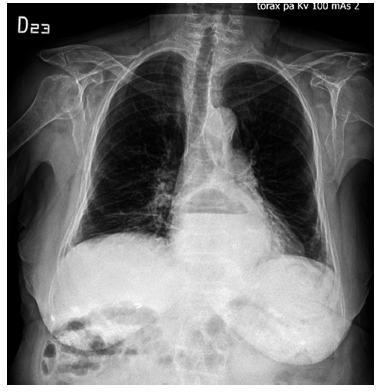

Se solicitó radiografía de tórax al ingreso por sospecha de fractura a nivel vertebral, donde se encuentra como hallazgo incidental ascenso de la cámara gástrica en el mediastino posterior, asociado a nivel hidroaéreo, sugestivo de vólvulo gástrico (Figura 1).